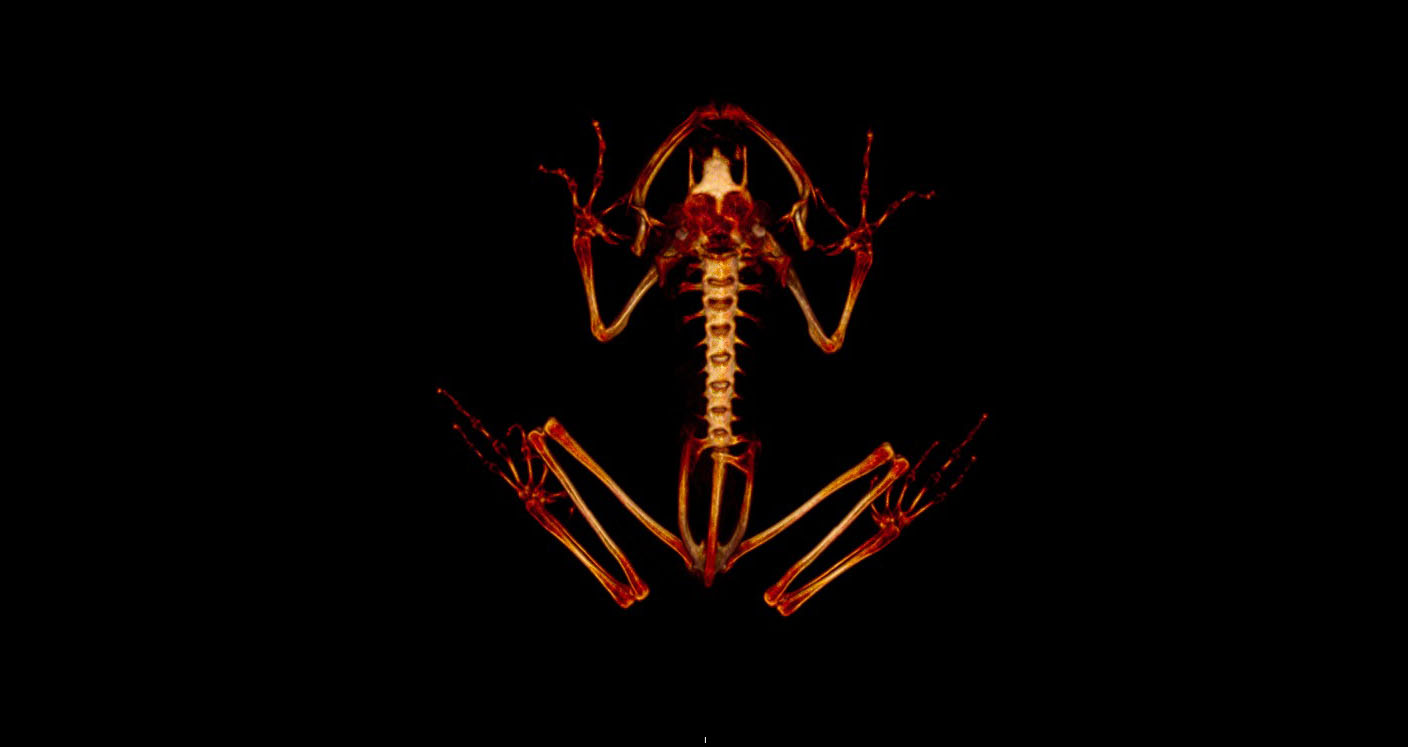

Lemur frog CT scan.

Aguilar has been studying how much food these frogs typically eat in a day and how to ensure they get enough calcium to keep their bones strong. In a recently published study, Aguilar and colleagues used micro-CT scans of live frogs to assess bone density and whether adding extra calcium to the insects the frogs ate could improve it.

The results were promising: the frogs on the higher calcium diet had higher bone density.

“We also found that how you determine bone density was very important, something that other studies should consider in the future,” said Mark Mitchell, professor of zoological medicine at LSU VetMed and senior author on the new study.

“Most studies only take a section of bone for the image, but Graciela ended up using the whole skeleton because these frogs are so tiny. This also helps prevent errors that occur when you only select one bone that may be remodeling at a different rate than other bones.”

The study helped Aguilar and colleagues determine how best to prepare foods for these critically endangered frogs in captivity, how to most accurately measure bone density over time, and how to successfully anesthetize the frogs for scanning without harming them.